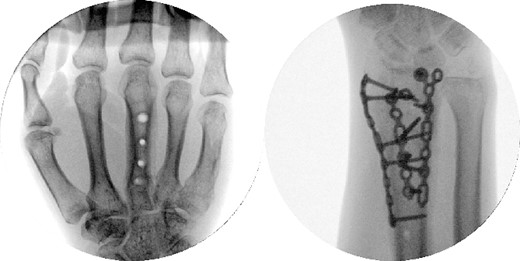

A 43-year-old man presented to the emergency department after falling ~5 ft from a ladder onto his outstretched right hand. He reported immediate pain and inability to bear weight through his right wrist. On physical examination, there was right wrist swelling and limited range of motion (ROM). The skin was intact, and neurovascular exam was normal. The patient had no other injuries and no pertinent medical history. Initial radiographic imaging confirmed a comminuted intra-articular distal radius fracture with dorsal displacement along with an ulnar styloid fracture (Fig. 1). The patient was placed in a sugar-tong splint and followed-up in clinic a week later with surgical treatment planned (Fig. 2).

Preoperative radiological assessment of the patient with postero-anterior (PA) and lateral views of the right wrist.